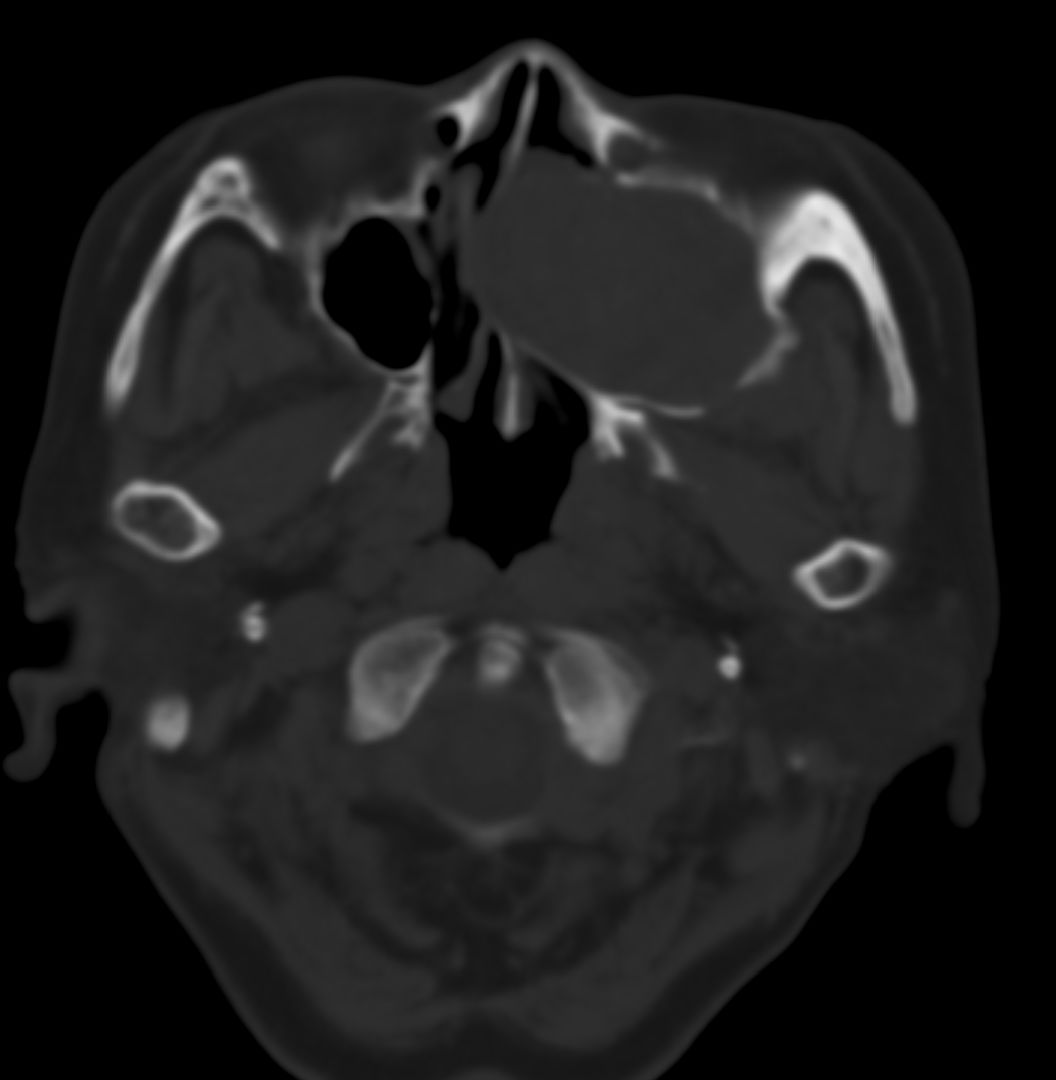

女,69岁。鼻出血2月多。(会诊病史就这样简单)鼻副窦ct检查如下:

左侧鼻腔及上颌窦见软组织块影,左侧上颌窦腔扩大,骨质吸收,右侧上颌窦见半圆形软组织密度影,鼻中隔向右侧弯曲,左侧鼻和鼻窦内翻型乳头状瘤可能性大,建议增强。

左侧上颌窦及鼻腔内见软组织密度影,其内密度不均匀,见斑片状高密度影,右侧上颌窦腔明显扩大,窦壁吸收变薄,鼻中隔右偏,右侧上颌窦见一半圆形软组织密度影,边界清楚,其内密度均匀。诊断,1、左侧鼻腔及上颌窦内翻乳头状瘤可能性大,上颌窦癌,息肉及霉菌性上颌窦炎待除外。2、右侧上颌窦粘膜下囊肿。

窦腔密度不均匀增高,无明显钙化征象,后外侧及内侧窦壁膨胀明显,局部破坏消失,筛窦受累及,但双侧对比发现左侧窦壁骨质有硬化增白现象,这可能是支持左侧霉菌性上颌窦炎的主要依据点。